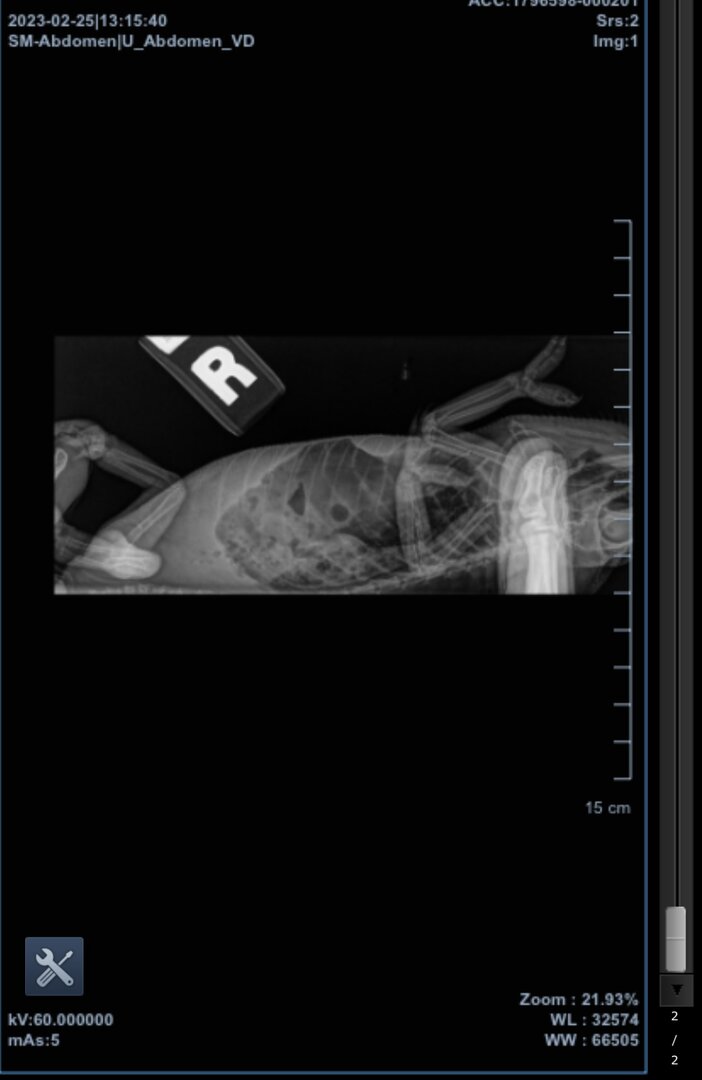

I took her to a vet who takes exotics, and got her checked and x-rayed. The doctor didn't seem too knowledgable on chameleons, and told me quickly that if she had already laid her eggs, she probably wasn't egg bound and likely didn't have any left inside her. She agreed that my girl was plump, though, and recommended we go ahead with the x-ray. I'll post them here for y'all to see as well, but she didn't see any eggs in there, and told me Reggie might have gas (?) inside her, but didn't elaborate much, just sent us on our way.

I wonder if any of you can see the egg in these x-rays, because I don't know if I can. There is one circular blob that doesn't look like an egg at all compared to other cham x-rays, but maybe that was it in the end, I'm not sure. I included a comparison x-ray I found on google that shows many eggs, so I know it's not the best to compare Reggie's to, but the little blob in her second view of her abdomen doesn't look like as opaque as the eggs in the comparison.

You were right, the x-ray did not show the last remaining egg very clearly at all. Honestly, the vet visit was kind of pointless, and I will try and get in touch with a herp vet in the future instead of a general vet who happens to take exotics.